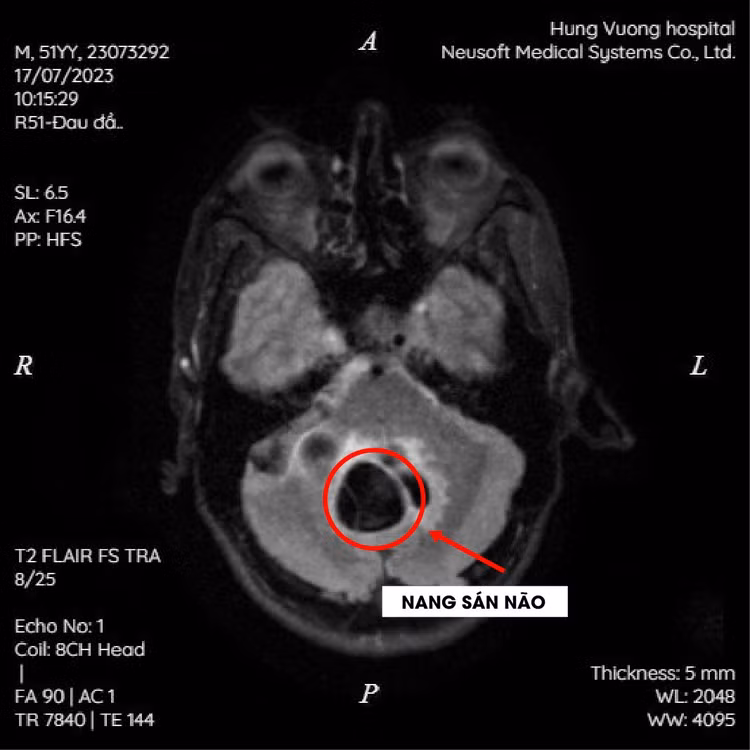

Hai bệnh nhân được xét nghiệm đánh giá tìm căn nguyên, tương đồng hơn nữa là kết quả chụp MRI sọ não đều tổn thương dạng nang trong nhu mô não theo dõi nang sán và kết quả ELISA dương tính với sán dây chó (Echinococus).

| Hình ảnh tổn thương nan sán trong não trên phim chụp |

Các bác sĩ chẩn đoán cả 2 bệnh nhân bị Nang sán não (cerebral hydatid cysts) do sán dây chó (Echinococus) được theo dõi và điều trị theo đúng phác đồ.